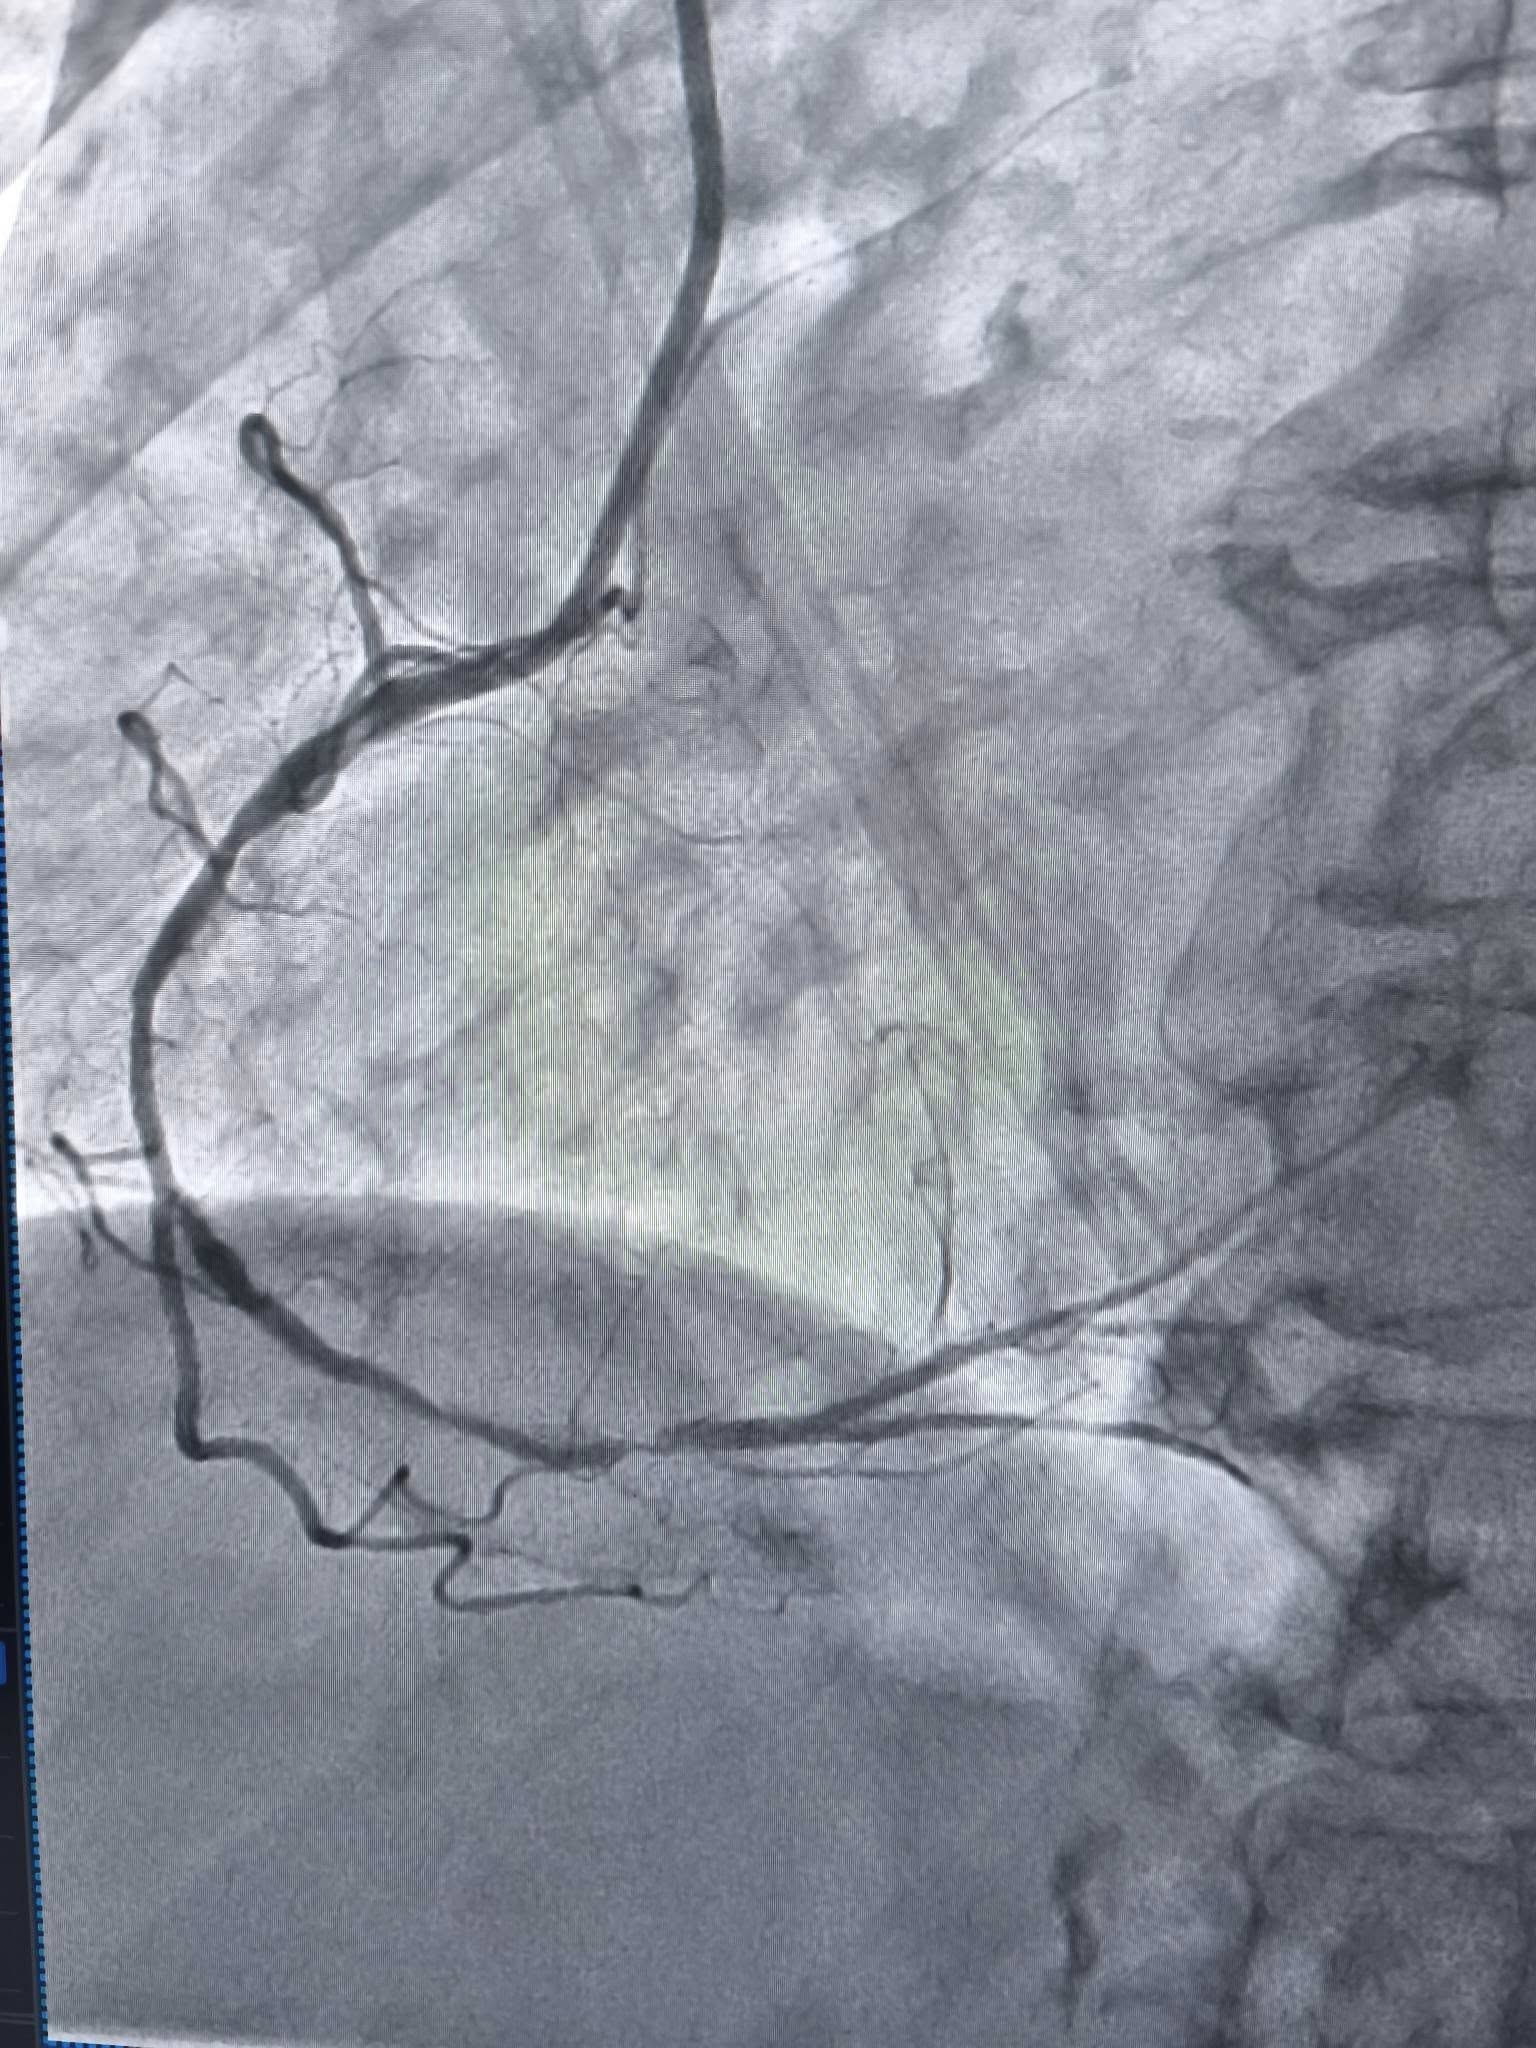

За словами завідувача відділенням інтервенційної радіології, кардіології та реперфузійної терапії Богдана Маслія, у пацієнтки діагностували значне звуження правої коронарної артерії.

Саме таким методом лікарям вдалося ліквідувати перешкоду в артерії та успішно імплантувати стенти.